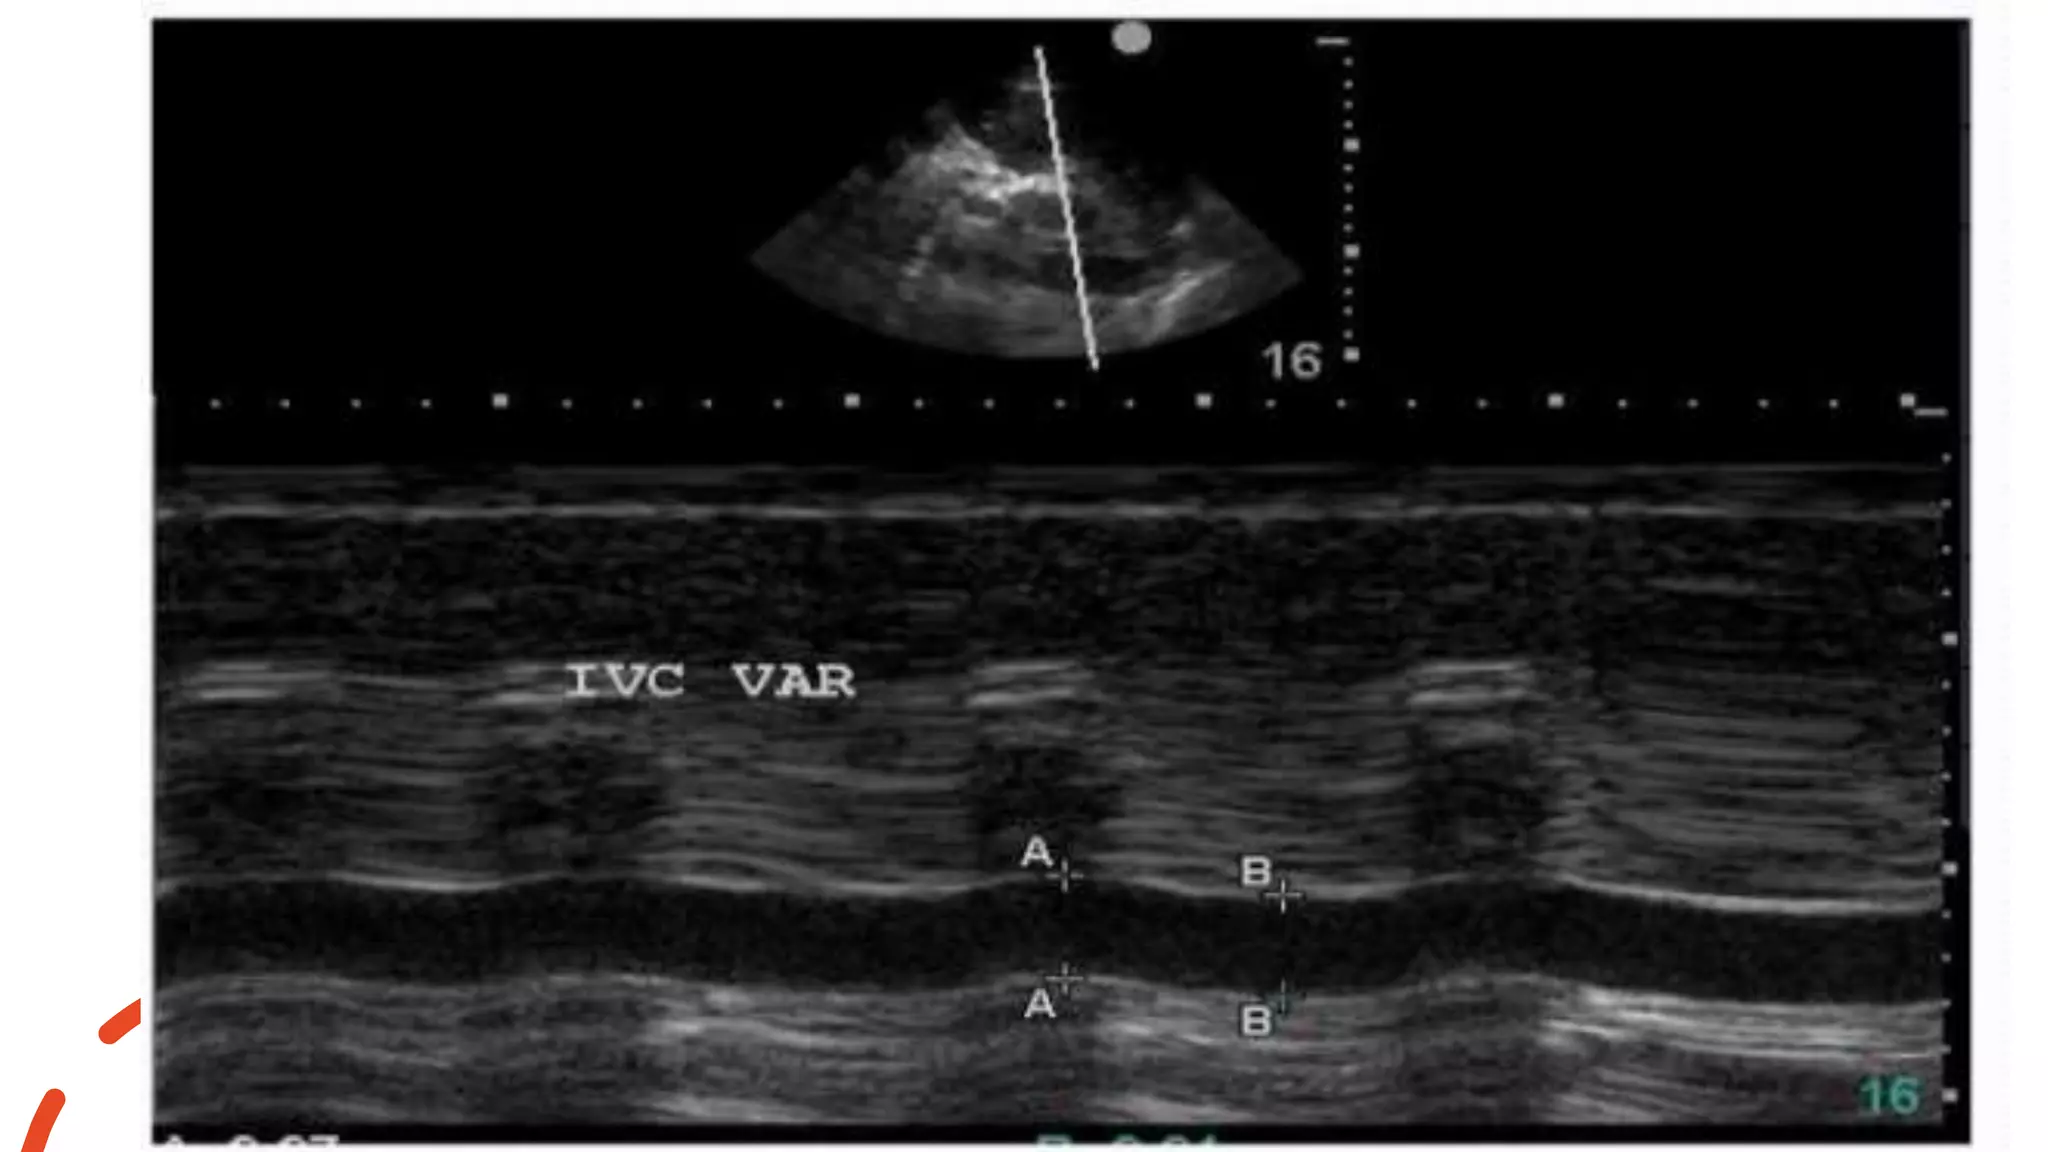

inferior vena cavaplethora (maximum diameter ≥21 mm and degree of inspiratory collapse <50%

• Dilated IVC with blunted respiratory changes

inferior vena cava plethora (maximum diameter ≥21 mm and degree of